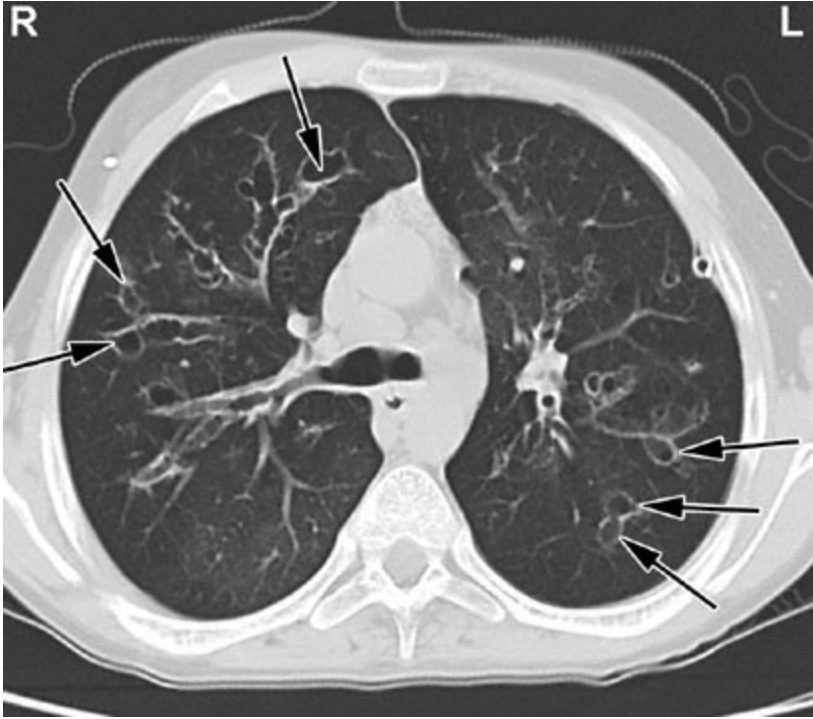

A 5-year-old boy is brought to the physician by his parents as a new patient because they are concerned that he may have an immunodeficiency. The family recently moved to the area. The parents say their son’s previous physician had been examining him for the condition. The patient has had six episodes of pneumonia and 10 episodes of sinusitis since birth. He underwent uncomplicated surgical drainage of the sinuses at the ages of 3 and 4 years. He had his first episode of otitis media at the age of 2 months and underwent uncomplicated placement of tympanostomy tubes at the age of 7 months. His umbilical stump fell off at the age of 2 weeks. The patient’s previous leukocyte, lymphocyte, and platelet counts; serum immunoglobulin and CH50 concentrations; and diphtheria, tetanus, pneumococcal, and Haemophilus influenzae type b titers are within the reference ranges. Six previous chest x-rays showed lower lobe consolidations in inconsistent locations; subsequent x-rays showed clearing of the infiltrates. Today, vital signs are within normal limits. Examination shows no abnormalities. A CT scan of the chest is shown. Which of the following is the most likely diagnosis?